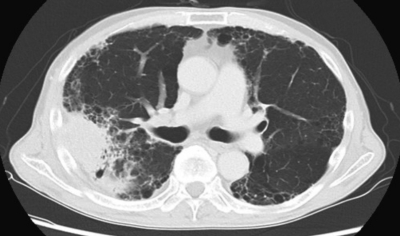

体温 36.6 ℃。脈拍 76/分、整。血圧 132/76 mmHg。呼吸数 12/分。SpO2 95 % (room air)。両側胸部で fine crackles を聴取する。呼吸機能検査:VC 3.5 L、FEV1 2.2L。心電図、心エコー検査で異常を認めない。胸部エックス線写真及び胸部単純CTを別に示す。